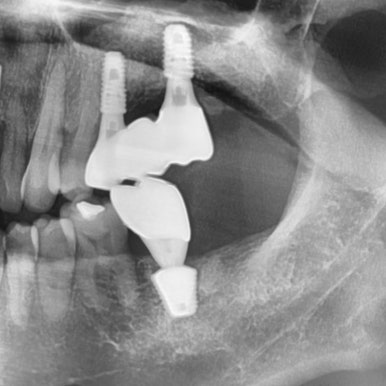

빨간색 화살표로 표시한 부분의 인플란트 주변 뼈가 녹아서 임플란트가 흔들리는 상태였습니다.

아마 고난도의 상악동 거상술이 필요해서 다른 치과에서 임플란트를 뼈가 그나마 있는 화살표 부분에만 심었던 것 같습니다.

간단한 상악동 수술이 아니라 복잡한 고난이도의 상악동 수술이 필요했는데

상악동을 들어올려 뼈이식을 하고(노란색으로 표시된 부분)

임플란트 2개를 심은 모습입니다. [②로 표시된 부분]

나머지 ①③ 표시된 부분도 원장님께 임플란트 수술을 받으셨습니다.

④로 표시된 부분은 사랑니 발치한 부분입니다.

원장님께 수술 받은 3군데 임플란트 5개 모두 잘 쓰고 계십니다.